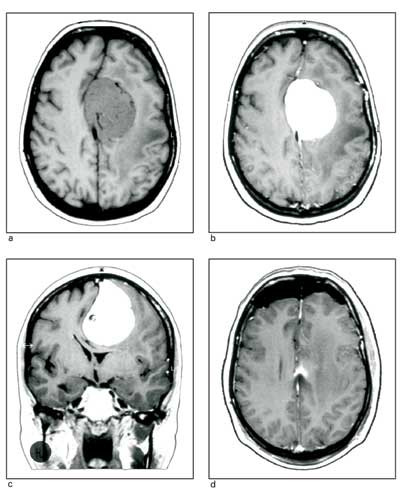

Astrocytomer.Disse utgår fra astrocytter. Lavgradig astrocytom, anaplastisk astrocytom og glioblastom er undergrupper med økende malignitetsgrad. Glioblastomer er mest infiltrerende og vokser hurtigst, og er derfor mest maligne (fig 1). Det er godt samsvar mellom histologisk bilde og prognose. Glioblastom, som er vanligst, kan enten utvikles fra astrocytom av lavere grad (sekundært glioblastom) eller oppstå de novo (primært glioblastom). Pilocytisk astrocytom er en variant av lavgradig astrocytom som, til forskjell fra de ovenstående, er en velavgrenset, langsomtvoksende svulst hos barn og unge voksne uten tendens til malign degenerasjon. Den forekommer først og fremst i cerebellum, n. opticus og hypothalamus.

Meningeomer. Disse utgjør 20 % av primære intrakraniale svulster. Forekomsten øker med alderen, og det er en overvekt av kvinner (1,7 : 1). Kvinner med meningeom har en lett overhyppighet av brystkreft og vice versa, antakelig fordi begge svulstformer er påvirkelige av kvinnelige kjønnshormoner. Meningeomene oppstår fra araknoidale celler og er godartet hos 95 %. De er velavgrenset og omgitt av en kapsel, og skyver hjernen foran seg under veksten (fig 2). Dura er som regel infiltrert, av og til også tilgrensende deler av kraniet. De vokser vanligvis langsomt. Hjernen kan tilpasse seg veksten, derfor kan pasientene ha appelsinstore svulster før de får klare symptomer.

Dette er som regel godartede, velavgrensede svulster som vokser langsomt. Ved små svulster, som gir lite eller ingen plager, må man derfor overveie om man skal operere. Dersom pasienten er gammel eller skrøpelig og forventet livslengde kort, kan det være riktig å observere vedkommende med regelmessige CT- eller MR-kontroller. Kirurgi bør først vurderes dersom tumorvekst kan forringe/forkorte pasientens liv. Det samme gjelder ved akustikusnevrinomer. Hvis man opererer, tilstreber man radikal operasjon. Dette er oftest mulig ved meningeomer på hjernens konveksitet, falx cerebri, laterale kilebeinsvinge eller frontobasalt (fig 2). Radikal operasjon kan være vanskeligere eller umulig ved meningeomer som affiserer sinus sagittalis, den cerebellopontine vinkel, sinus cavernosus eller clivus. Etter makroskopisk radikal operasjon får ca. 10 % residiv innen ti år, og ved subtotal reseksjon vil mer enn 50 % få betydelig vekst av restsvulsten i dette tidsrom (32). Radikalopererte skal ikke ha strålebehandling. Etter subtotal reseksjon bør man overveie stereotaktisk ekstern bestråling av restsvulst (33). Konvensjonell bestråling kan også gis ved restsvulst (34), men pga. senskader foretrekker vi stereotaktisk bestråling når dette er mulig. Ved anaplastiske/maligne meningeomer er residivfrekvensen betydelig hyppigere, derfor er man mer liberal med stråleterapi. Tiårsoverlevelsen for pasienter med meningeom er 96 % (korrigert for annen dødsårsak) (35).